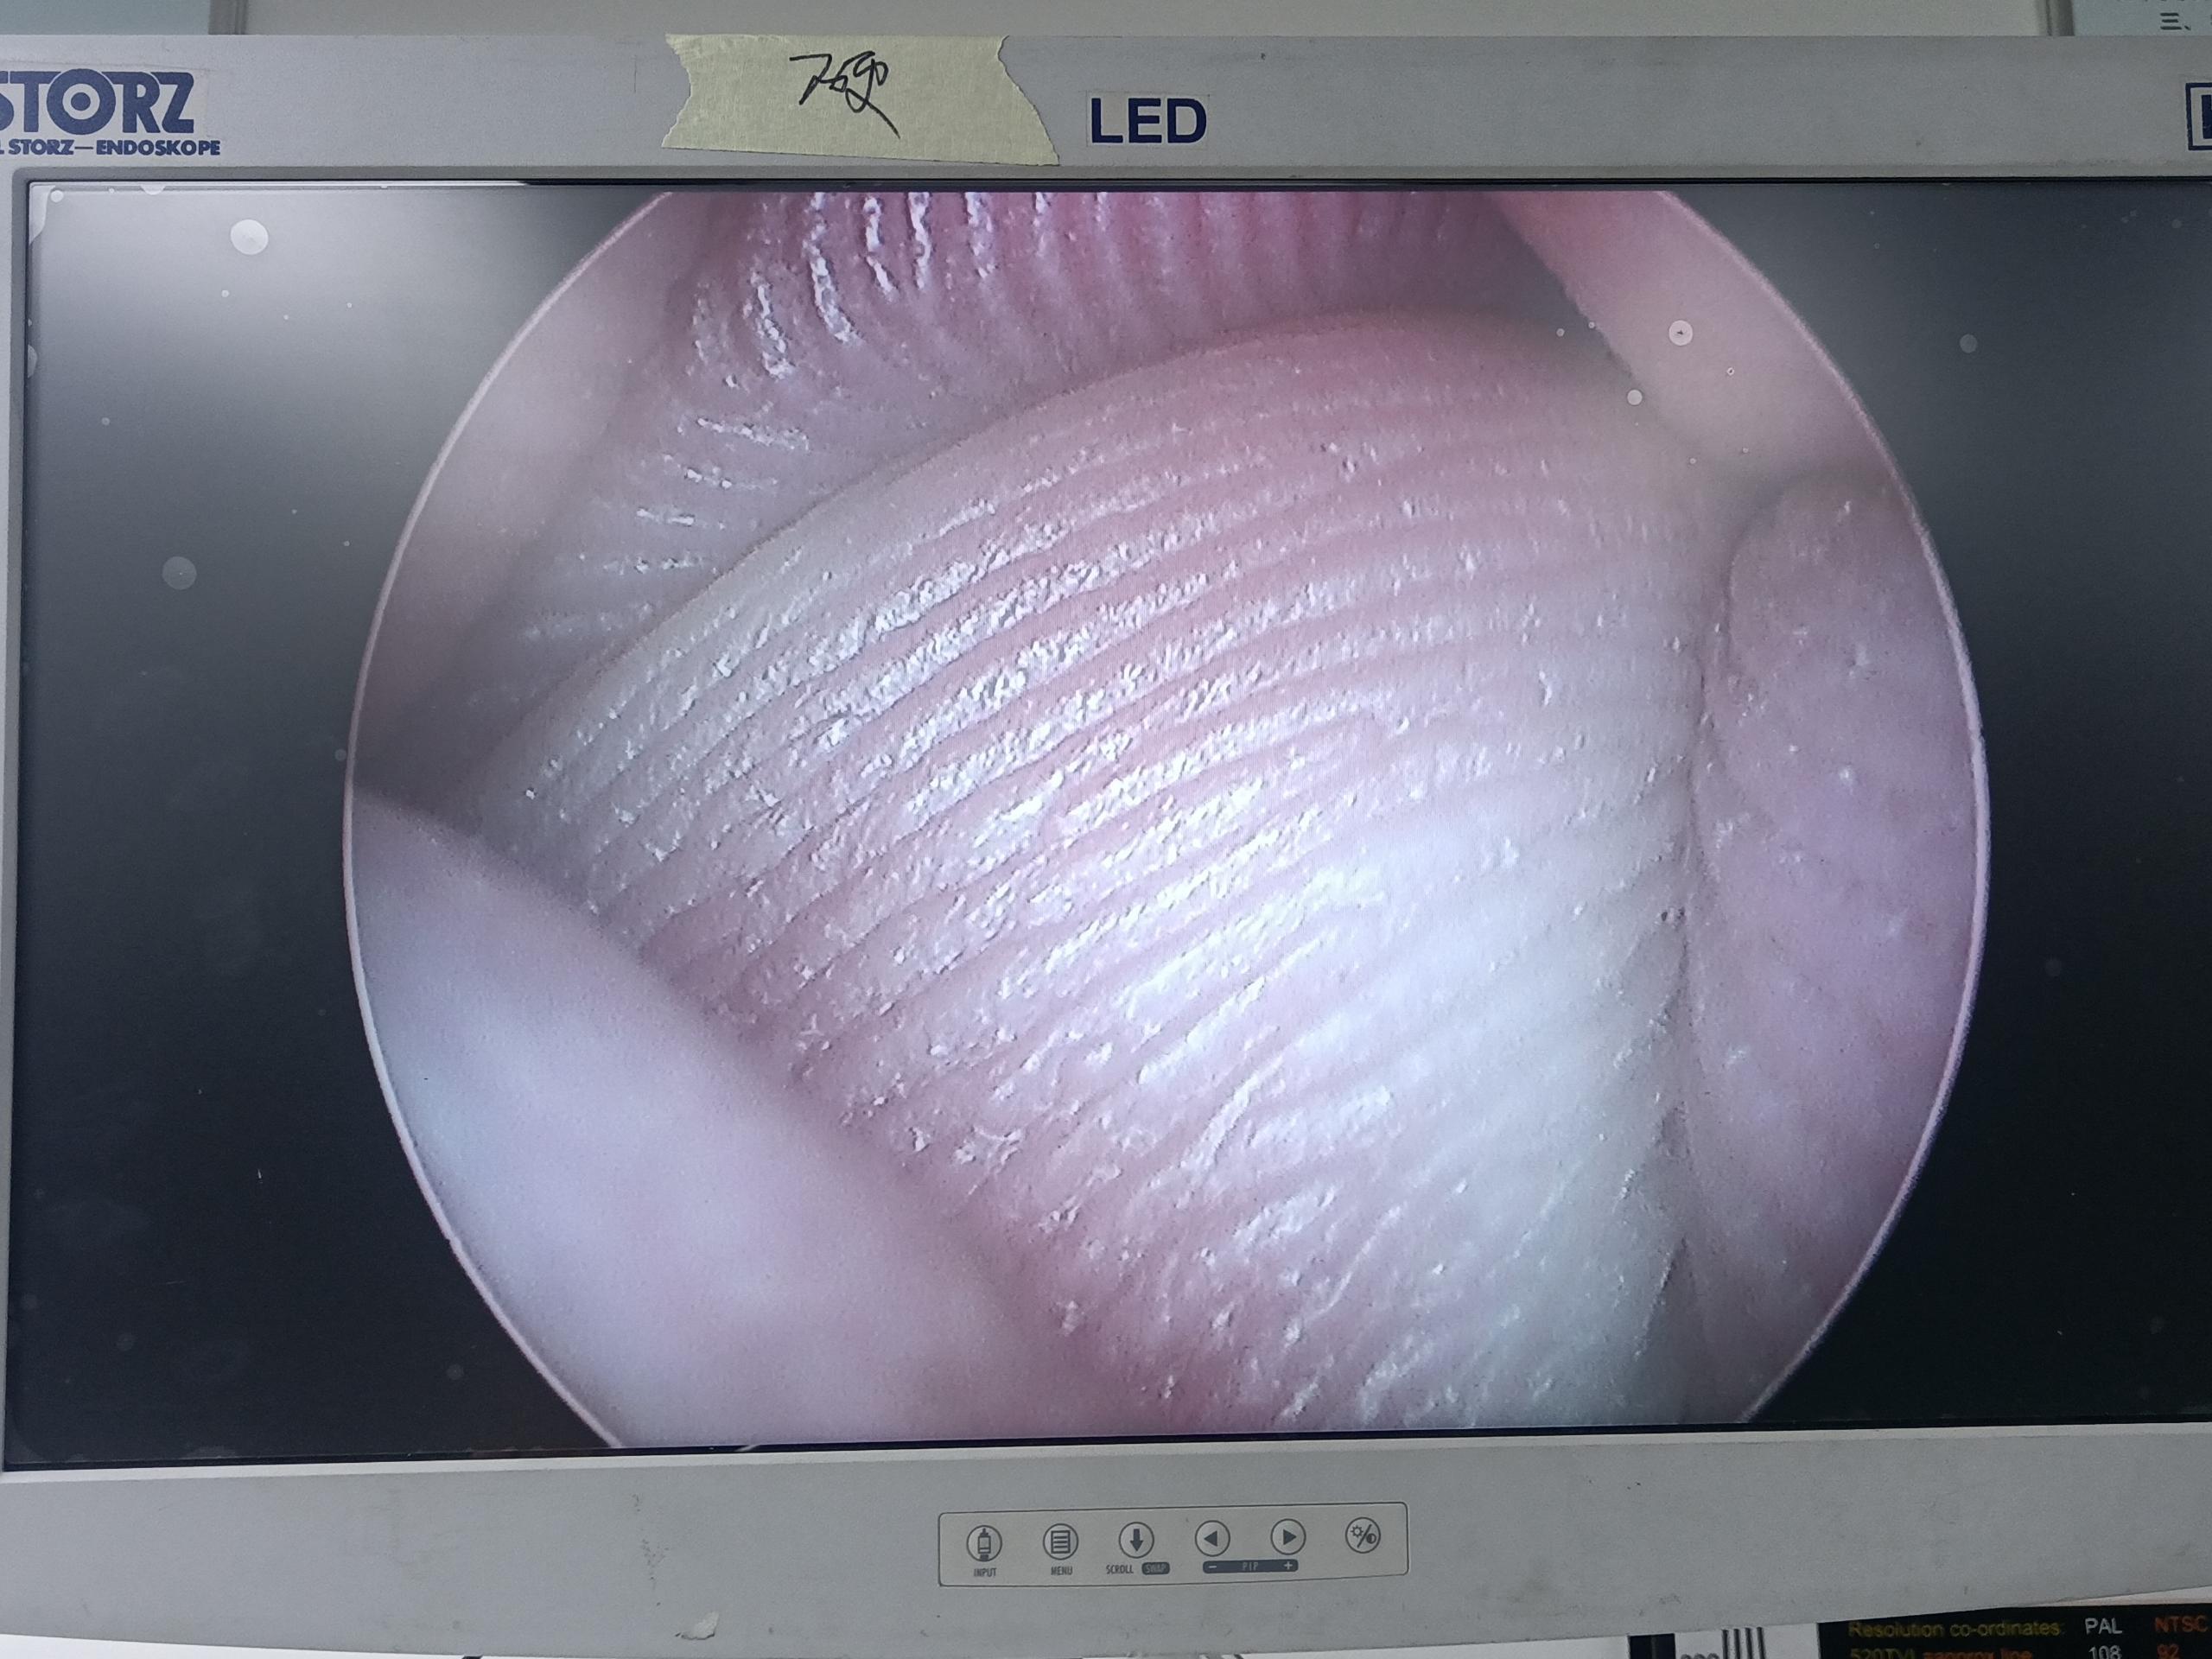

設(shè)備型號(hào)Wolf狼牌電切鏡8650.414

故障內(nèi)容圖像模糊,棒透鏡破碎,導(dǎo)光錐破碎,目鏡罩破碎,鏡身有磕碰,但不影響使用。

維修方案更換棒透鏡、導(dǎo)光錐、目鏡罩,校對(duì)圖像,內(nèi)窺鏡抗震蕩抗沖擊性能測試,內(nèi)窺鏡密封性性能檢測;內(nèi)窺鏡抗震蕩性能測試,內(nèi)窺鏡冷熱沖擊性能檢測。